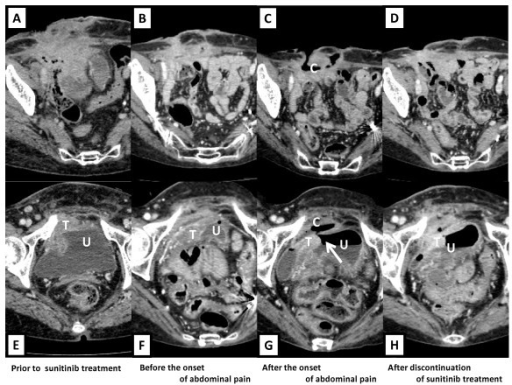

Question Understanding [Uncaptioned image] Question: Considering the affected region’s relationship with adjacent structures, which aspect most clearly supports the significance of the subtle finding? Options: A) A focal mural discontinuity at the posterior bladder wall contiguous with the tumor, consistent with a tiny bladder dome perforation. B) A minute defect at the inferior (neck) aspect of the anterior bladder wall adjacent to the lesion suggesting intraperitoneal communication. C) A small defect at the anterior bladder wall adjacent to the lesion. D) A minute defect at the inferior (neck) aspect of the anterior bladder wall adjacent to the lesion suggesting intraperitoneal communication. E) A minute defect at the lateral anterior bladder dome adjacent to the lesion. Correct Answer: C Model Answer: E Model Reasoning: The question asks which imaging detail, based on how the lesion relates to nearby structures, best confirms the clinical importance of a subtle CT finding. Serial axial CT images show a pelvic mass abutting the urinary bladder. At the lateral anterior bladder dome, right where the mass contacts the bladder wall, a minute defect in the bladder wall at that site. This focal defect at the dome adjacent to the lesion most strongly indicates a small but clinically important breach or early communication. Other observations either occur at locations that do not relate to the dome or do not show this discrete dome defect, so they lack the same direct anatomic relevance. Error Interpretation: The model did not ground its interpretation in the specific structural detail that the question was designed to assess. It shifted the abnormality toward a dome-based location and responded as if the finding were meant to highlight a lateral dome defect, which is not what the question described. By doing so, it effectively answered a different question than the one asked. This indicates a question understanding error.